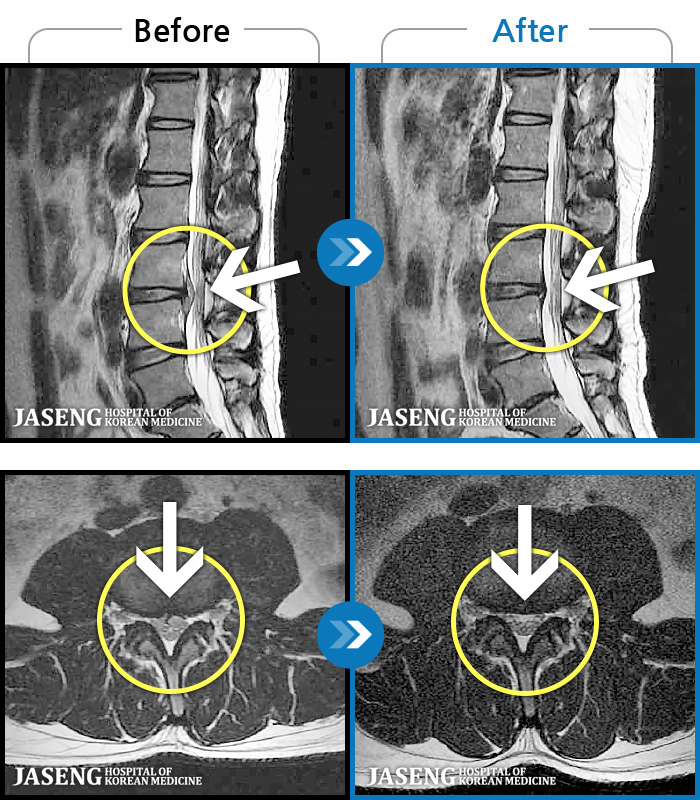

[] 03.04.01~09.11.01